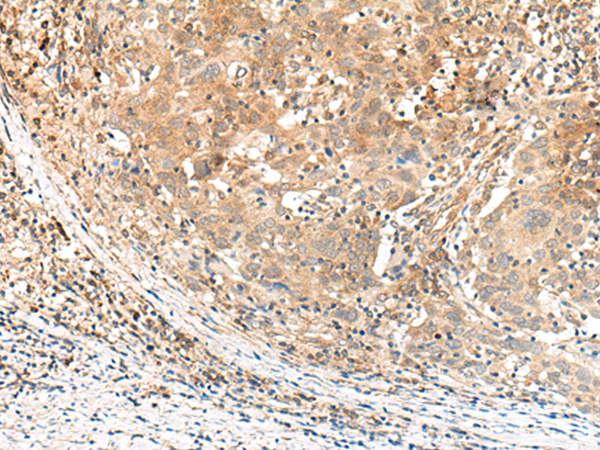

IHC positive control: |

Human cervical cancer |

IHC Recommend dilution: |

30-150 |